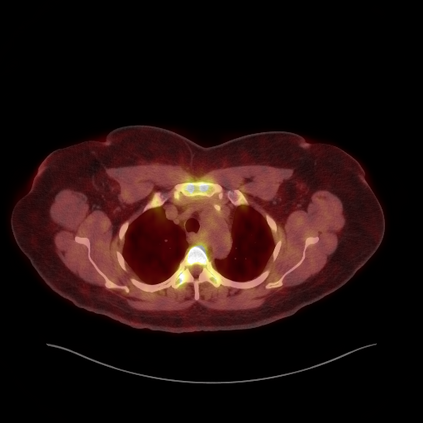

Medical images play a crucial role in assisting diagnosis, remote consultation, and academic research. However, during the transmission and sharing process, they face serious risks of copyright ownership and content tampering. Therefore, protecting medical images is of great importance. As an effective means of image copyright protection, zero-watermarking technology focuses on constructing watermarks without modifying the original carrier by extracting its stable features, which provides an ideal approach for protecting medical images. This paper aims to propose a fragile zero-watermarking model based on dual quaternion matrix decomposition, which utilizes the operational relationship between the standard part and the dual part of dual quaternions to correlate the original carrier image with the watermark image, and generates zero-watermarking information based on the characteristics of dual quaternion matrix decomposition, ultimately achieving copyright protection and content tampering detection for medical images.